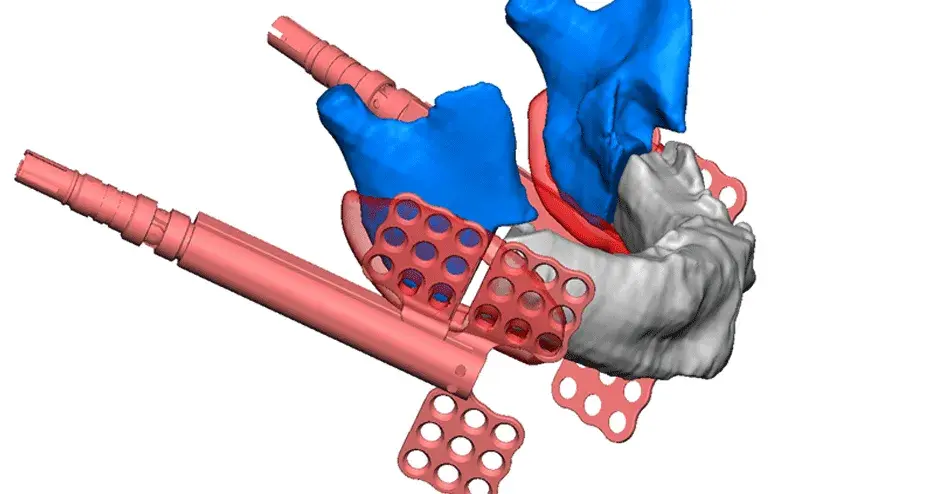

3D Systems' VSP® surgical planning solutions for craniomaxillofacial (CMF) applications received FDA clearance as a service-based approach to personalized surgery over 10 years ago.

3D Systems and Stryker Corporation have partnered to provide surgeons with best-in-class products and services for craniomaxillofacial surgeries. As a leader in personalized healthcare solutions, 3D Systems has planned and delivered devices for more than 140,000 patient-specific cases. The Stryker Craniomaxillofacial business specializes in providing patient-specific options and innovative solutions that help drive efficiencies in surgical suites. The combination of Stryker’s specialized team and advanced implants with 3D Systems' cutting-edge 3D printing technologies and expert consulting services positions both companies to provide a superior level of service to healthcare professionals who use these revolutionary solutions.